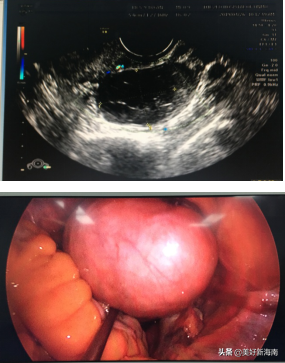

该例患者是一名子宫肌瘤的患者,肌瘤瘤体较大(10cm),已出现月经量增多及压迫症状等不适,需手术调节。患者有强烈保留子宫意愿,因患者是疤痕体质,特别担心手术后留下疤痕,坚决要求微创手术调节。经过检查及评估,科室讨论后,决定为其实施经脐单孔腹腔镜下子宫肌瘤剔除术+子宫整形术。患者手术过程顺利,因腹壁切口很小,患者术后几乎没感觉到伤口的疼痛。